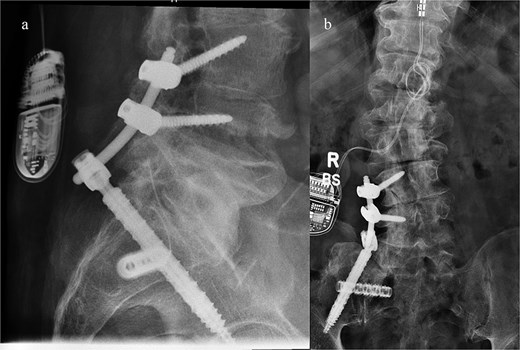

A CT of the pelvis showed significant hyperostosis along the anterior right SI joint and a pseudoarthrosis between the L5 transverse process and the sacral ala that was osteoblastic-appearing in nature (Fig. 1). A SPECT-CT demonstrated increased uptake along the same area, suggestive of inflammatory degenerative changes (Fig. 2).

Coronal CT pelvis (left) and axial (right) demonstrated hyperostosis along the right SI joint suggestive of an osteoblastic lesion between the L5 transverse process and sacral ala (arrows).